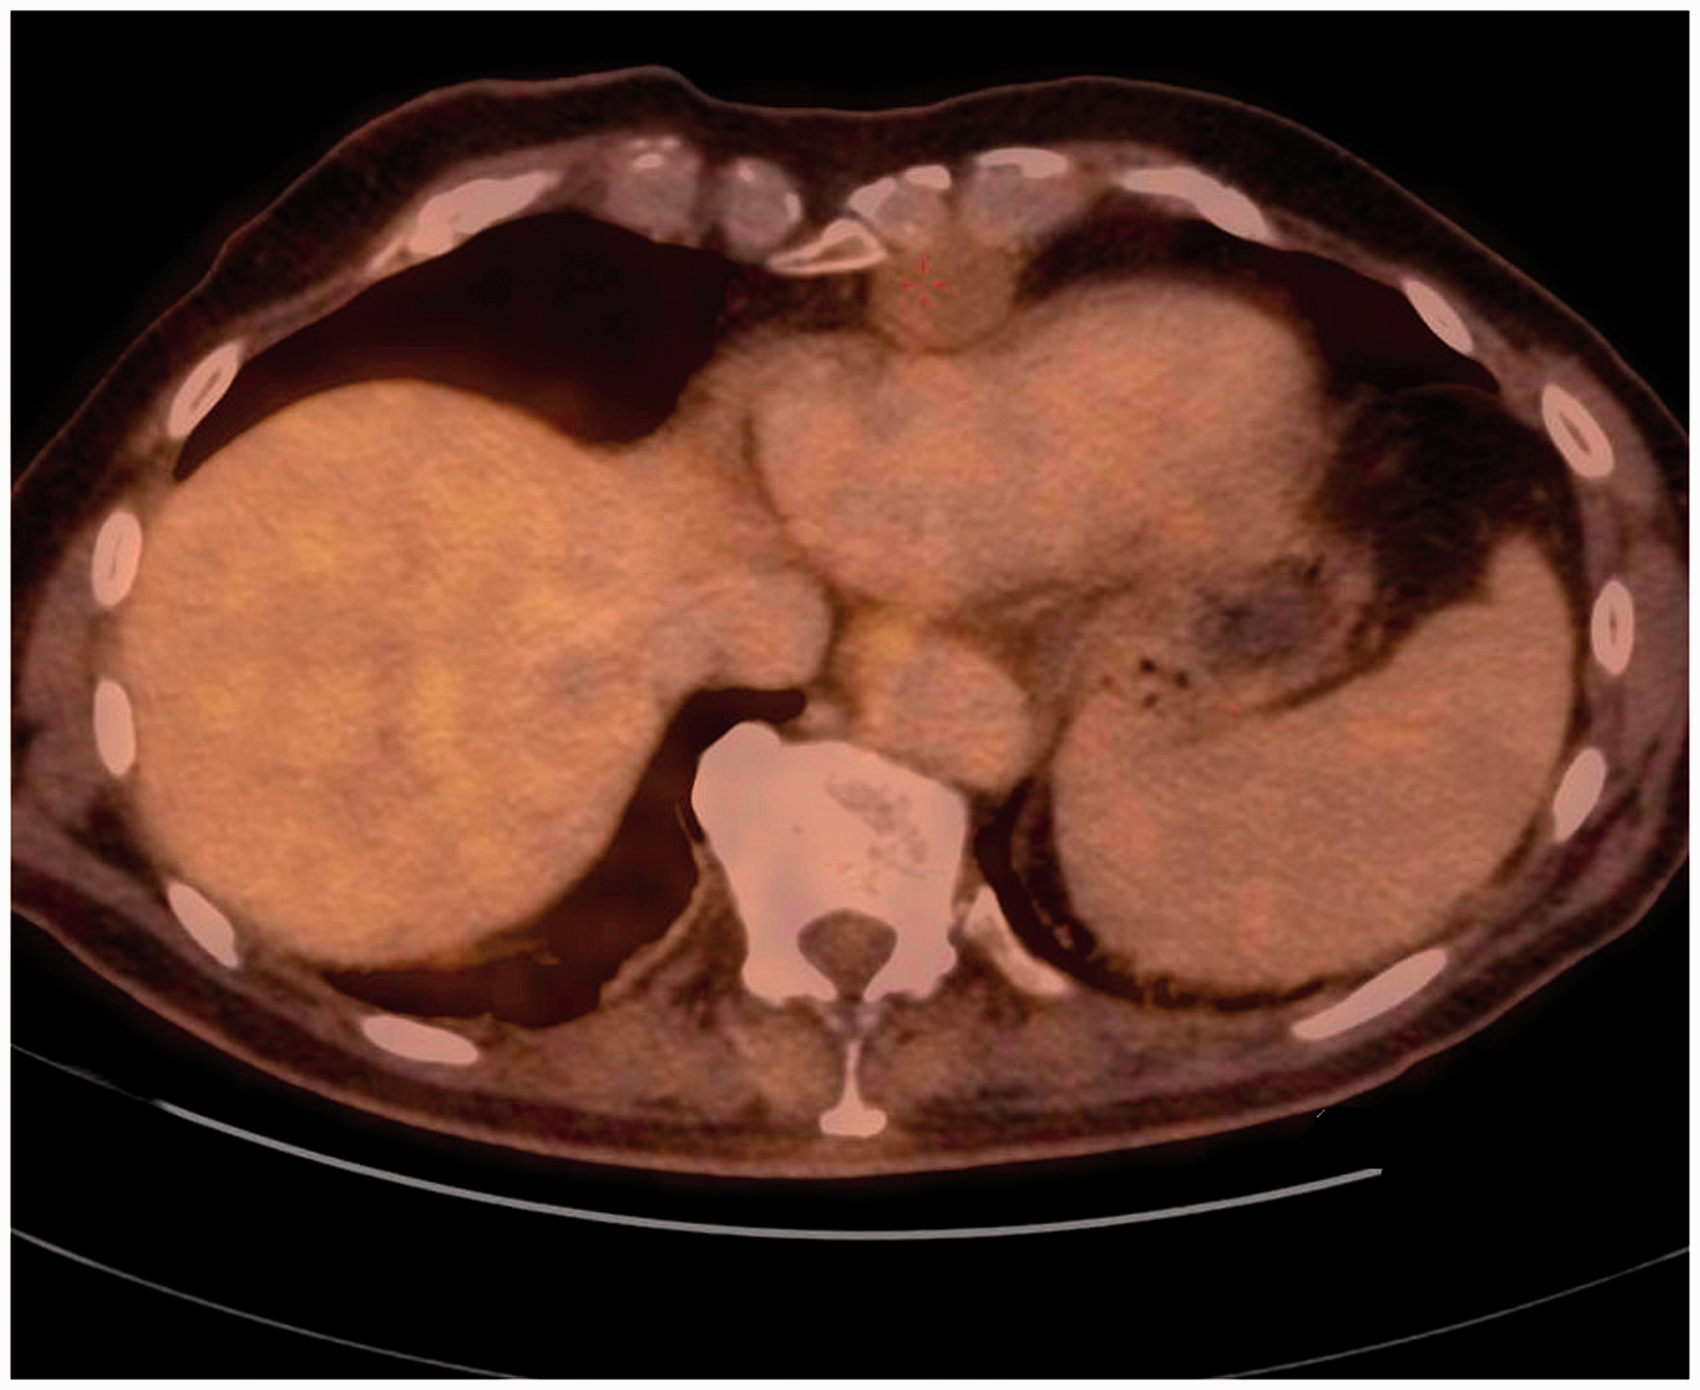

CT revealed a 4.3 × 2.6 × 3.3 cm, round, well-defined tumor with smooth borders in the anterior mediastinum with close relation to the ribs (Fig. 1). A low dose CT scan had been performed 4 years earlier, where the tumor had been overlooked (Fig. 2). Since then it had doubled its size. Positron emission tomography (PET-)CT was performed and showed a mean standardized uptake value of 1.57 with a maximum of 1.89 in the tumor indicating a low risk of malignancy. A thymoma was considered as diagnosis (Fig. 3). A neurophysiological examination was performed due to suspicion of myasthenia gravis, but did not reveal any abnormalities. No laboratory findings could support the suspicion of myasthenia. The tumor was not accessible for CT-guided biopsy and it could not be diagnosed on ultrasound due to poor visualization. Despite the lack of positive laboratory findings for myasthenia, the patient was referred under the diagnosis of myasthenia gravis for surgical removal of the suspected thymoma.

Second CT scan of the chondrosarcoma. Tumor makes a slight compression of the heart. CT scan of the chondrosarcoma performed 4 years prior to diagnosis. Tumor is visible anterior to the heart, but unfortunately overlooked. PET-CT scan showing a slight FDG uptake in the tumor with a minor compression of the heart.